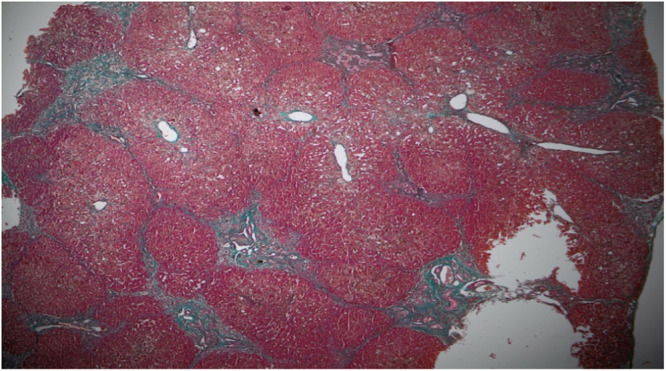

最近发现的一种与ZFYVE19基因突变有关的非综合征表型,其特征是出现胆汁淤积,并伴随婴儿期或幼儿期血清γ -谷氨酰转肽酶(GGT)升高。受影响的个体通常表现为肝脾肿大,并可能发展为门脉高压。该病被认为是胆管细胞特异性纤毛功能障碍的结果,表明纤毛病似乎仅限于肝脏。在这里,我们描述了一个一级近亲父母所生婴儿的病例,其中新生儿胆汁淤积伴随着GGT升高导致ZFYVE19缺乏症的发现。诊断是在对完整的外显子组测序进行深入分析后确定的。

A recent nonsyndromic phenotype, newly linked to mutations in the ZFYVE19 gene, is characterized by the appearance of cholestasis accompanied by an increase in serum gamma-glutamyltranspeptidase (GGT) from infancy or early childhood. Affected individuals generally present with hepatosplenomegaly and may develop portal hypertension. The disease is thought to be the result of cholangiocyte-specific ciliary dysfunction, indicating a ciliopathy that appears to be limited to the liver. Here, we describe the case of an infant born to first-degree consanguineous parents, in whom neonatal cholestasis accompanied by elevated GGT led to the discovery of a ZFYVE19 deficiency. The diagnosis was established following an in-depth analysis of the complete exome sequencing.